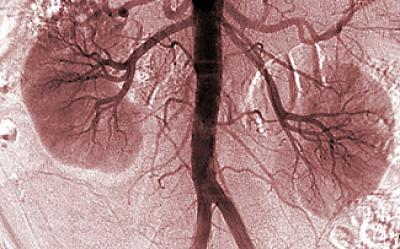

Researchers at the University of California, San Diego School of Medicine have identified 13 metabolites – small molecules produced by cellular metabolism – that are significantly different in patients with diabetes and chronic kidney disease compared to healthy controls.

Diabetic kidney disease is the leading cause of end-stage kidney disease, which is the eighth leading cause of death in the United States and a major risk factor for cardiovascular disease, the nation's leading killer. An estimated 26 million American adults have chronic kidney disease (CKD), with millions more at increased risk. These patients often require dialysis or an organ transplant.

After analyzing a total of 193 urine samples from patients with diabetes and CKD, diabetes but no CKD and healthy controls with neither condition, Sharma and colleagues quantified 94 metabolites in the samples. Thirteen metabolites were significantly different between patients with diabetes and CKD versus controls. Twelve remained significant when compared to patients with diabetes but not CKD. Twelve metabolites play a role in mitochondrial metabolism and were present in lower levels in patients with diabetes and CKD, suggesting that this major diabetic complication is at least partly the consequence of suppressed mitochondrial activity.